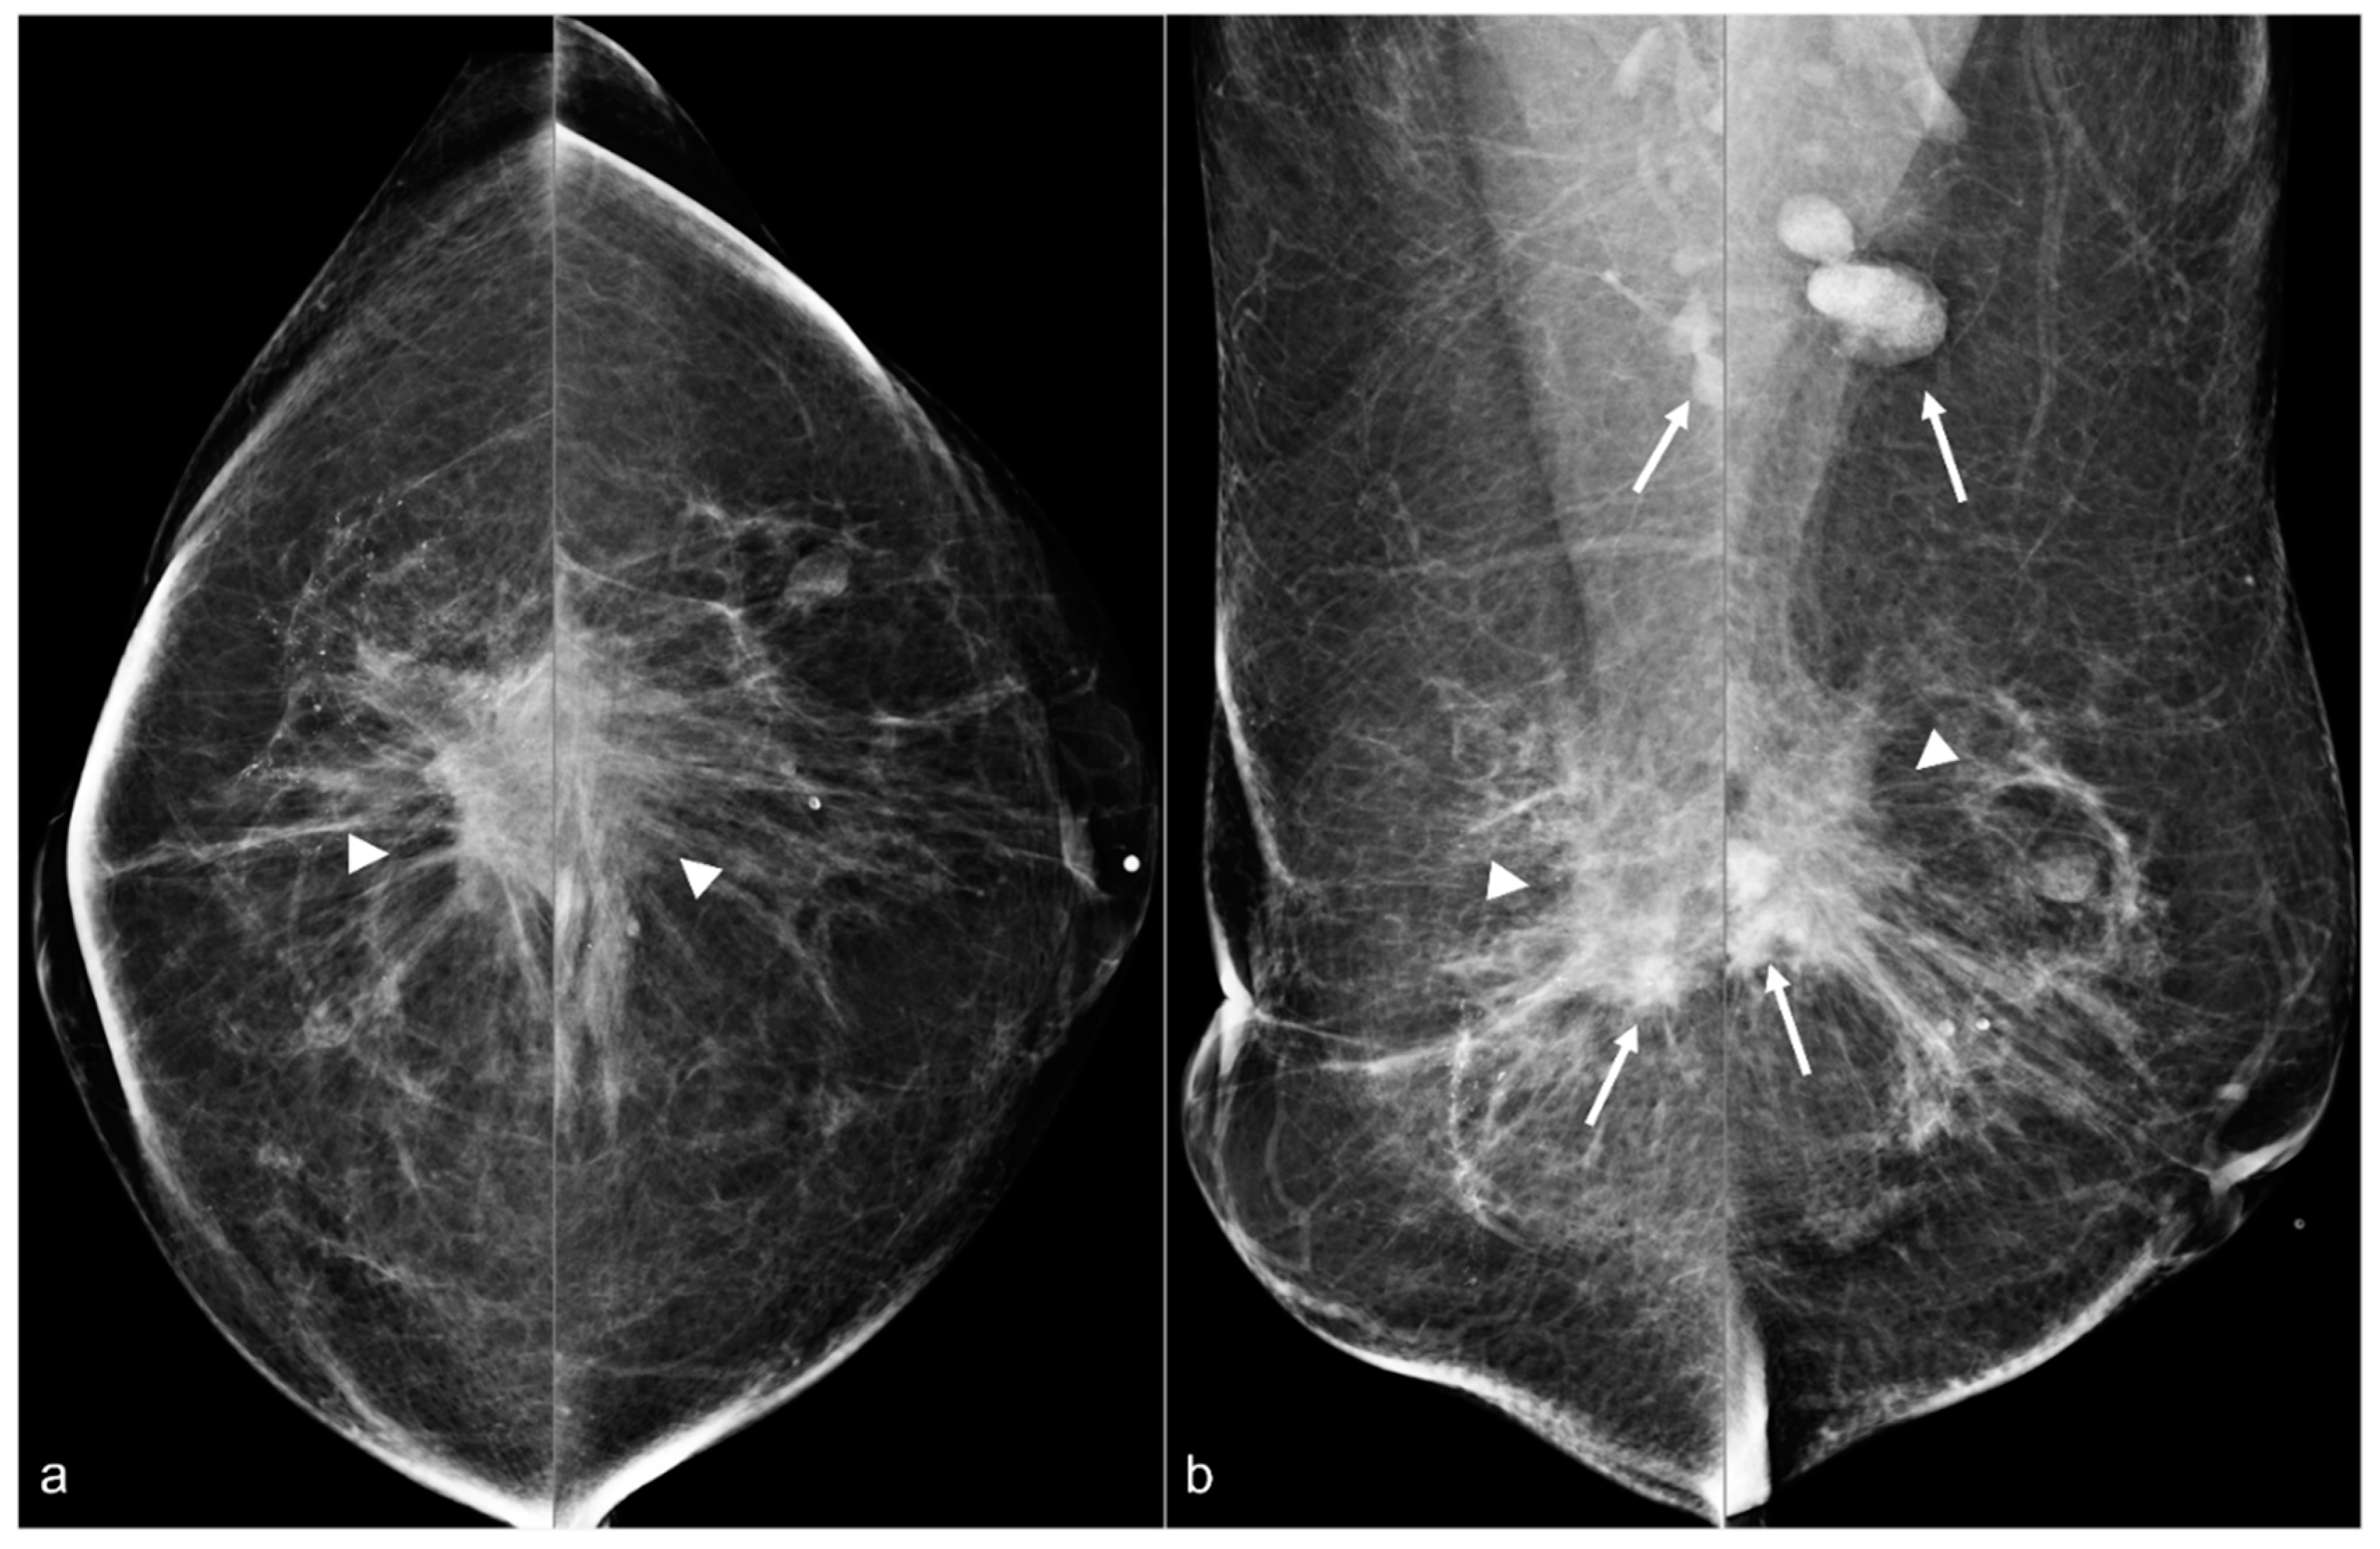

Figure 9. A 64-year-old woman status post BES due to silicone implant rupture. Spiculated masses (arrowheads) are seen in the pre-pectoral region on bilateral CC (a) and MLO (b) views. Hyperdense material (arrows) in both surgical beds and the bilateral axillae are sequelae of prior silicone implant rupture.